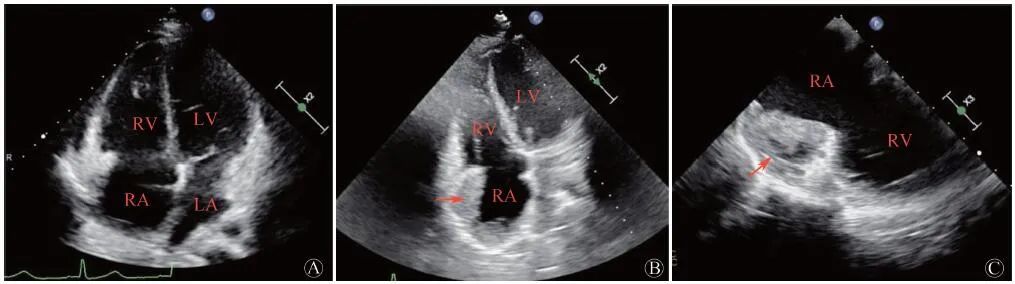

患者行TEE提示右心房及心包内可见多处中低回声团块影,最大位于近右房室沟,大小约49 mm×25 mm,其内血流丰富,并再次观察TTE,在非标准切面显示右房占位(图2 )。考虑肿瘤性病变可能性大。胸部增强CT见右心部分心包增厚,右心房、房间隔多发富血供占位,部分明显强化,部分成分强化不明显,不除外血栓形成(图3 )。PET/CT躯干断层显像:右心房增大,形态欠规则,密度不均匀,右心房、右心室及相邻心包脂肪间隙代谢不均匀异常增高,SUVmax 11.9,不除外恶性病变可能;T2椎体左后方肌间隙代谢增高灶,SUVmax 5.3,性质待定。颈胸椎旁肌肉MR增强及DWI成像均未见异常。

A:右心房形态不规则,可见多发软组织密度占位(箭头所示);B:右房、房间隔多发占位,部分明显强化,部分强化不明显(箭头所示),不除外血栓

图3 患者胸部增强CT图像